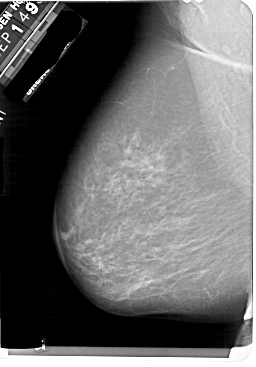

A_1858_1.RIGHT_MLO

RIGHT_MLO LINES 5491 PIXELS_PER_LINE 3811 BITS_PER_PIXEL 12 RESOLUTION 43.5 OVERLAY

FILE: A_1858_1.RIGHT_MLO.OVERLAY

TOTAL_ABNORMALITIES 1

ABNORMALITY 1

LESION_TYPE MASS SHAPE LOBULATED MARGINS ILL_DEFINED

ASSESSMENT 4

SUBTLETY 3

PATHOLOGY BENIGN